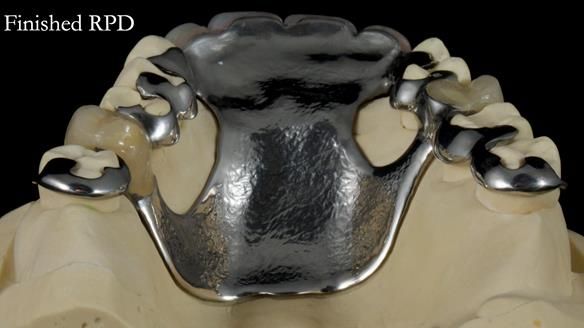

This is one of those cases that reminds me why I love removable prosthodontics. Pam was an absolute joy to treat — we were on the same page throughout. Her old upper flexible denture was loose, uncomfortable, and unaesthetic. We replaced it with a carefully designed metal-based upper partial denture/splint and new porcelain-bonded-to-zirconia (PBZ) crowns for the canines. The result is stable, comfortable, and natural-looking.

- Diagnosis and plan – Flexible upper denture ill-fitting with poor stability, retention, and appearance. Plan: metal-based upper partial denture/splint with lighter porcelain-bonded-to-zirconia crowns on UR3 and UL3.

- Metalwork framework try-in – to verify fit, path of insertion, and support.